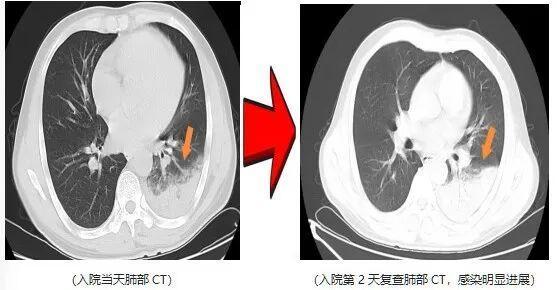

近日,一名爱鸟人士因持续高热、剧烈咳嗽,紧急就诊并收治于杭州萧山区中医院呼吸内科。入院后予以常规抗感染治疗2天,患者高热症状仍反复,最高体温升至40.5℃,伴干咳气促、夜间难以入眠,病情进展后更出现咯血及呼吸衰竭表现。